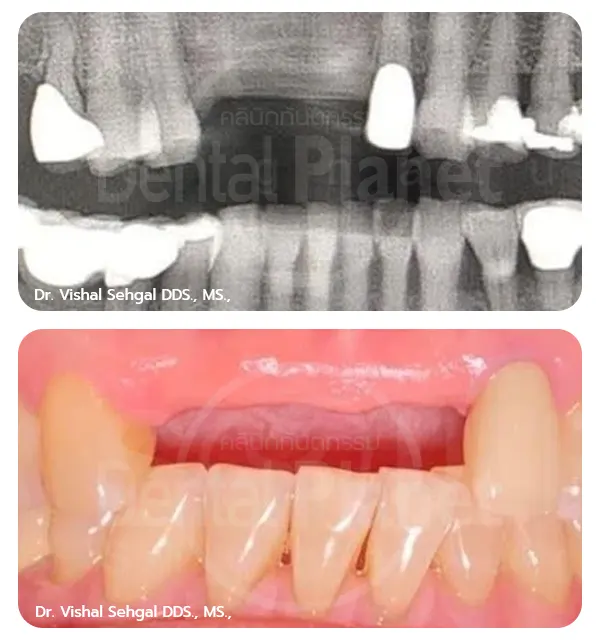

Before-After รากฟันเทียมฟันล่าง